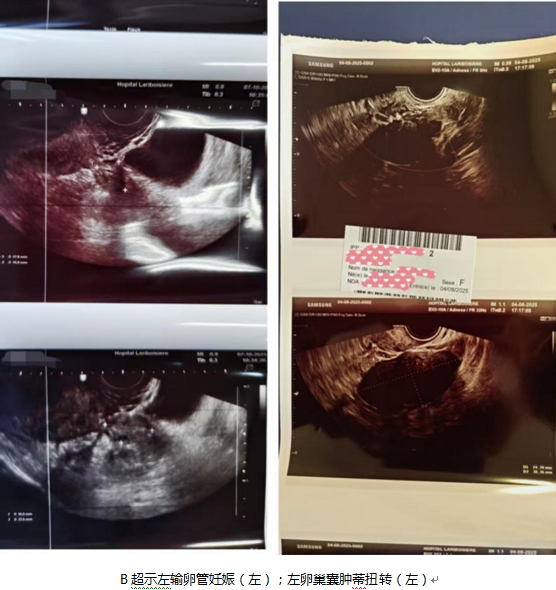

临床工作的具体流程更让我深感两国体系的迥异。与瑞金医院“管床”制不同,拉里布瓦西埃医院采用动态排班制:每日仅由一名住院医师负责整个妇科病房,并协同处理妇科急诊;另一名住院医师则与助产士团队共同管理产房、产科急诊及高危孕产妇病房;手术室则常规配备两人。每日早晨八点,妇产科全体成员,包括医师、助产士乃至文员,会共同参加长达45-60分钟的集中交班,逐一汇报病情并协调当日床位资源。这种高效但高强度的协作模式,要求住院医师在倾听与记录的同时,必须快速规划自己当日的工作重点。此外,妇产科超声的掌握过程,则充分体现了“在实战中成长”。在法国,超声检查主要由住院医师和助产士完成,上级医师仅负责关键的胎儿畸形筛查。然而,由于我此前在国内未曾独立操作,入科初期便被安排在急诊岗位,通过与全科医生协作,在大量的急诊病例中迅速积累了经验,最终成功独立识别出宫外孕、黄体破裂、卵巢囊肿蒂扭转等多种急/重症的超声征象。